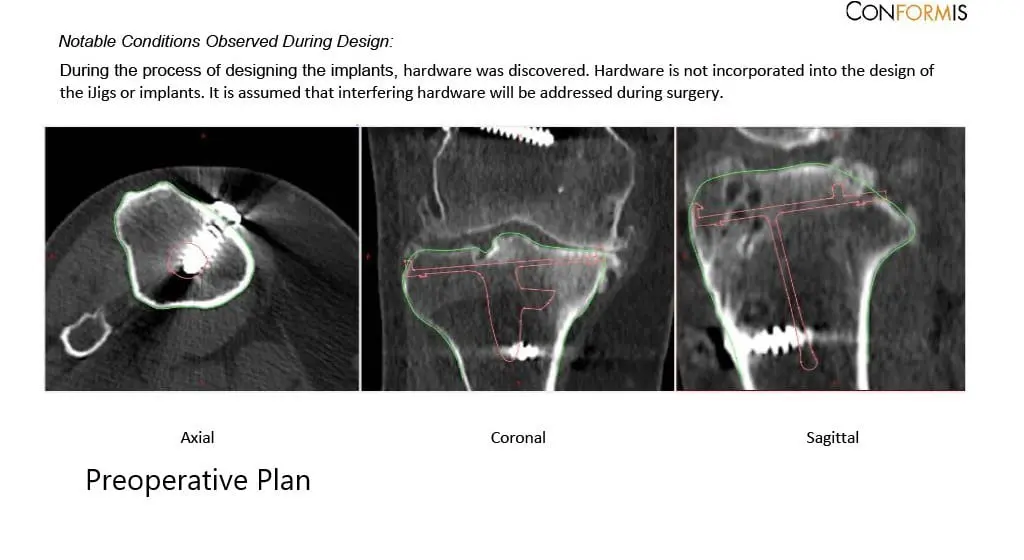

A preoperative CT scan obtained a few weeks prior to the procedure. The data was used to assess the patient’s unique anatomy and biomechanics. Customized unique patient-specific implants were made. Disposable bone cutting guides were 3D constructed to match the patient’s anatomy. A preoperative plan was formulated to guide the surgery.

Complete Orthopedics patient-specific surgical plan for a custom right total knee replacement in a 55-year-old female with Prior ACL Reconstruction.

Complete Orthopedics patient specific surgical plan for a custom right total knee replacement in a 55-year-old female with prior ACL Reconstruction (scan 2)